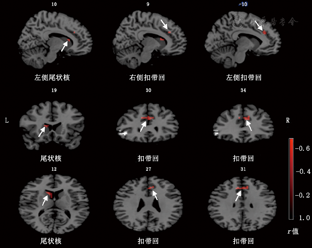

OCD患者的强迫行为与其左侧颞叶、双侧眶额叶、左侧额中回、右侧中央前回的ReHo值呈正相关(表3、图3)。

| 左侧颞叶 | 39 | 54 | -66 | 19 | 0.636 74 |

| 左侧眶额叶 | 45 | 54 | 34 | -2 | 0.620 64 |

| 右侧眶额叶 | 47 | -43 | 41 | -15 | 0.607 38 |

| 左侧顶叶 | 40 | 43 | -54 | 56 | 0.548 20 |

| 左侧额中回 | 8 | 34 | 10 | 59 | 0.664 73 |

| 右侧中央前回 | 6 | -58 | 3 | 35 | 0.732 29 |

OCD患者的强迫行为与其全双侧扣带回、左侧尾状核的ReHo值负相关(表4、图4)。

| 右侧扣带回 | 32 | -10 | 34 | 31 | -0.677 01 |

| 左侧扣带回 | 32 | 9 | 34 | 29 | -0.574 87 |

| 左侧尾状核 | 0 | 10 | 19 | 12 | -0.649 46 |